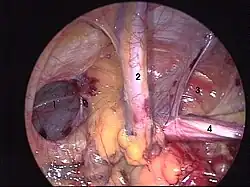

Ryc. 4 Śródoperacyjny widok przepukliny pachwinowej kombinowanej (tzw. pantaloon hernia). 1. komponenta przyśrodkowa 2. naczynia nabrzuszne dolne 3. kanał pachwinowy 4. powrózek nasienny